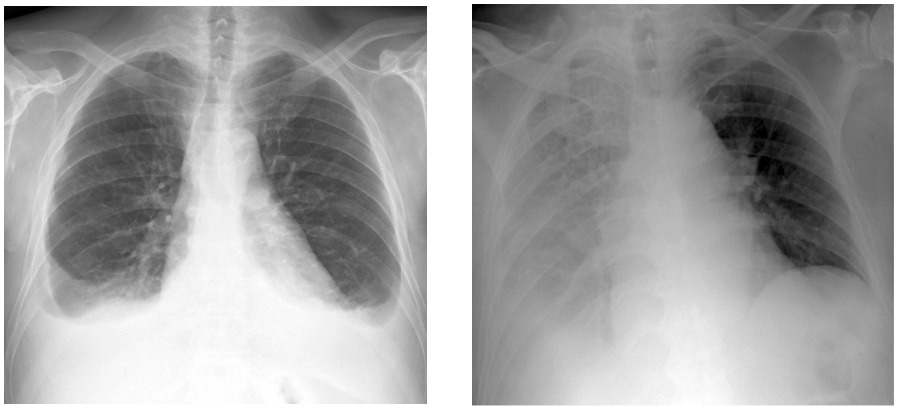

PadChest 是一个有标注的大型胸部 X 射线数据集,用于进行医学图像的自动探索。该数据集包括了 2009 至 2017 年间,圣胡安医院(西班牙)6.7 万位患者的 160 万多幅胸部 X 射线图像,涵盖了 6 个不同位置的视角,以及与图像获取与患者统计相关的补充信息。